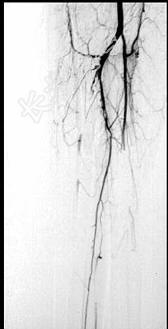

- 单项选择题43岁女性患者,突发左手疼痛伴多个指头麻木就诊, 行左上肢动脉照影,示左侧桡动脉广泛的充盈缺损, 结合临床考虑左侧桡动脉病变为 ( )

A、桡动脉夹层

B、桡动脉炎

C、桡动脉真性动脉瘤

D、桡动脉血栓形成

E、桡动脉假性动脉瘤